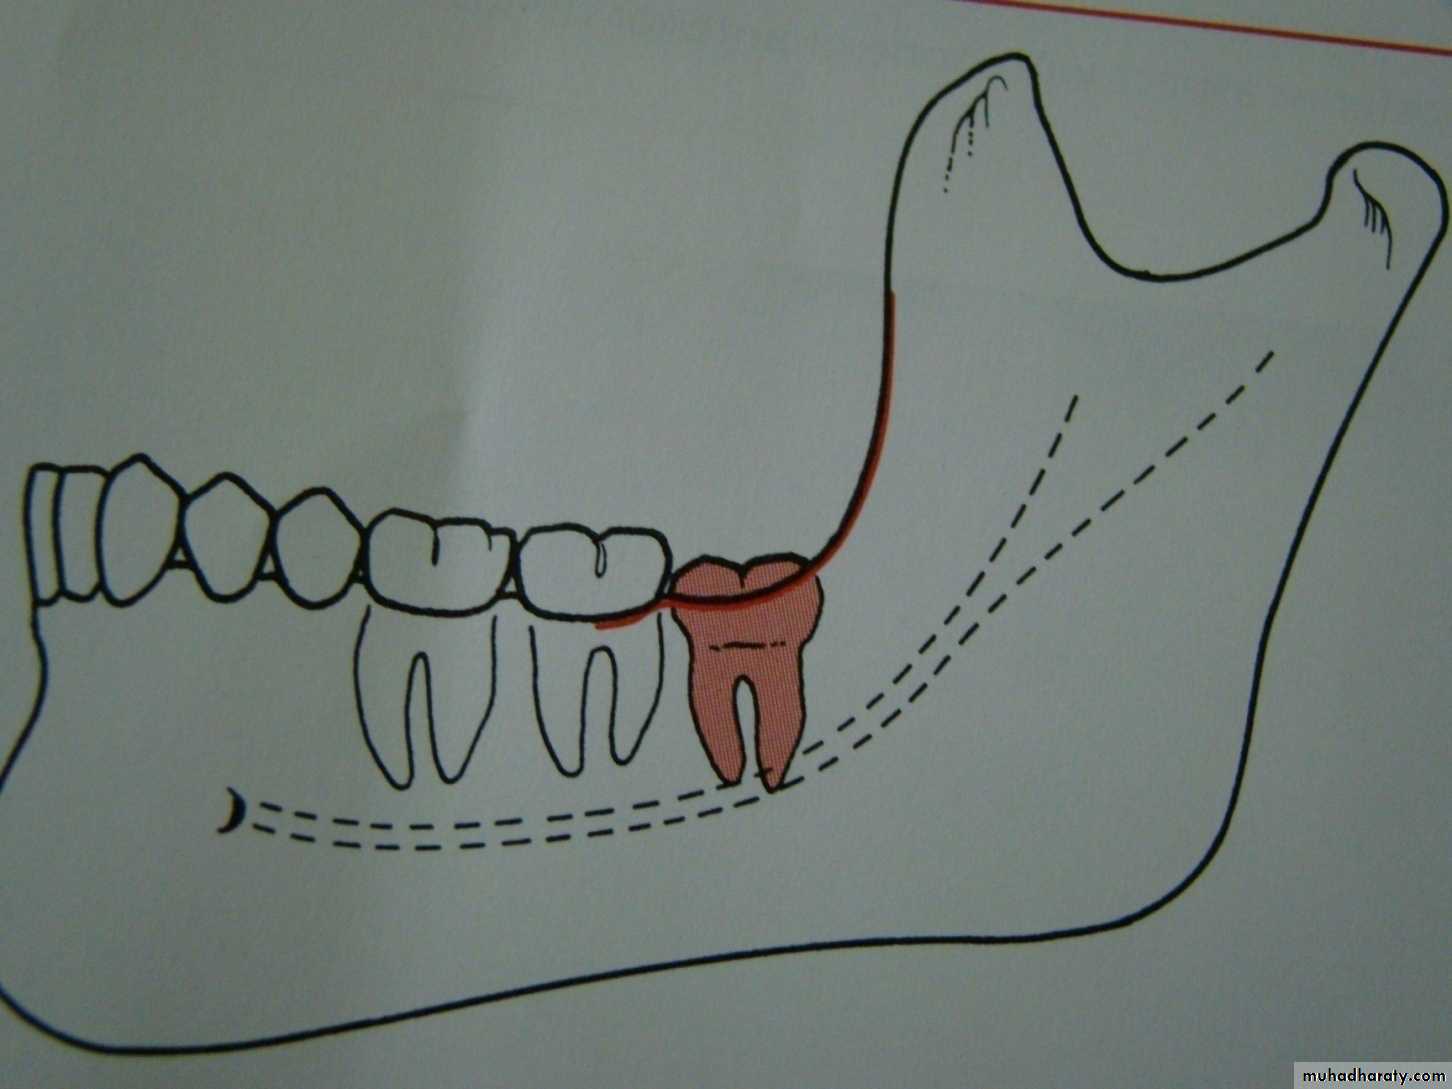

Relation of the impacted tooth to the anterior border of the ramus

Class 1 : the space between the lower second molar and the anterior border of the ramus is sufficient to accommodate the mesio distal dimension of the crown of the impacted lower third molarClass 2 : the space between the lower second molar and the ramus is insufficient to accommodate the crown of the impacted tooth .so part of it in the body and the other part lie in the ramus .

Class 3 the anterior border of the ramus lie near the distal surface of the lower second molar ,so ,the whole impacted tooth lie within the ramus .